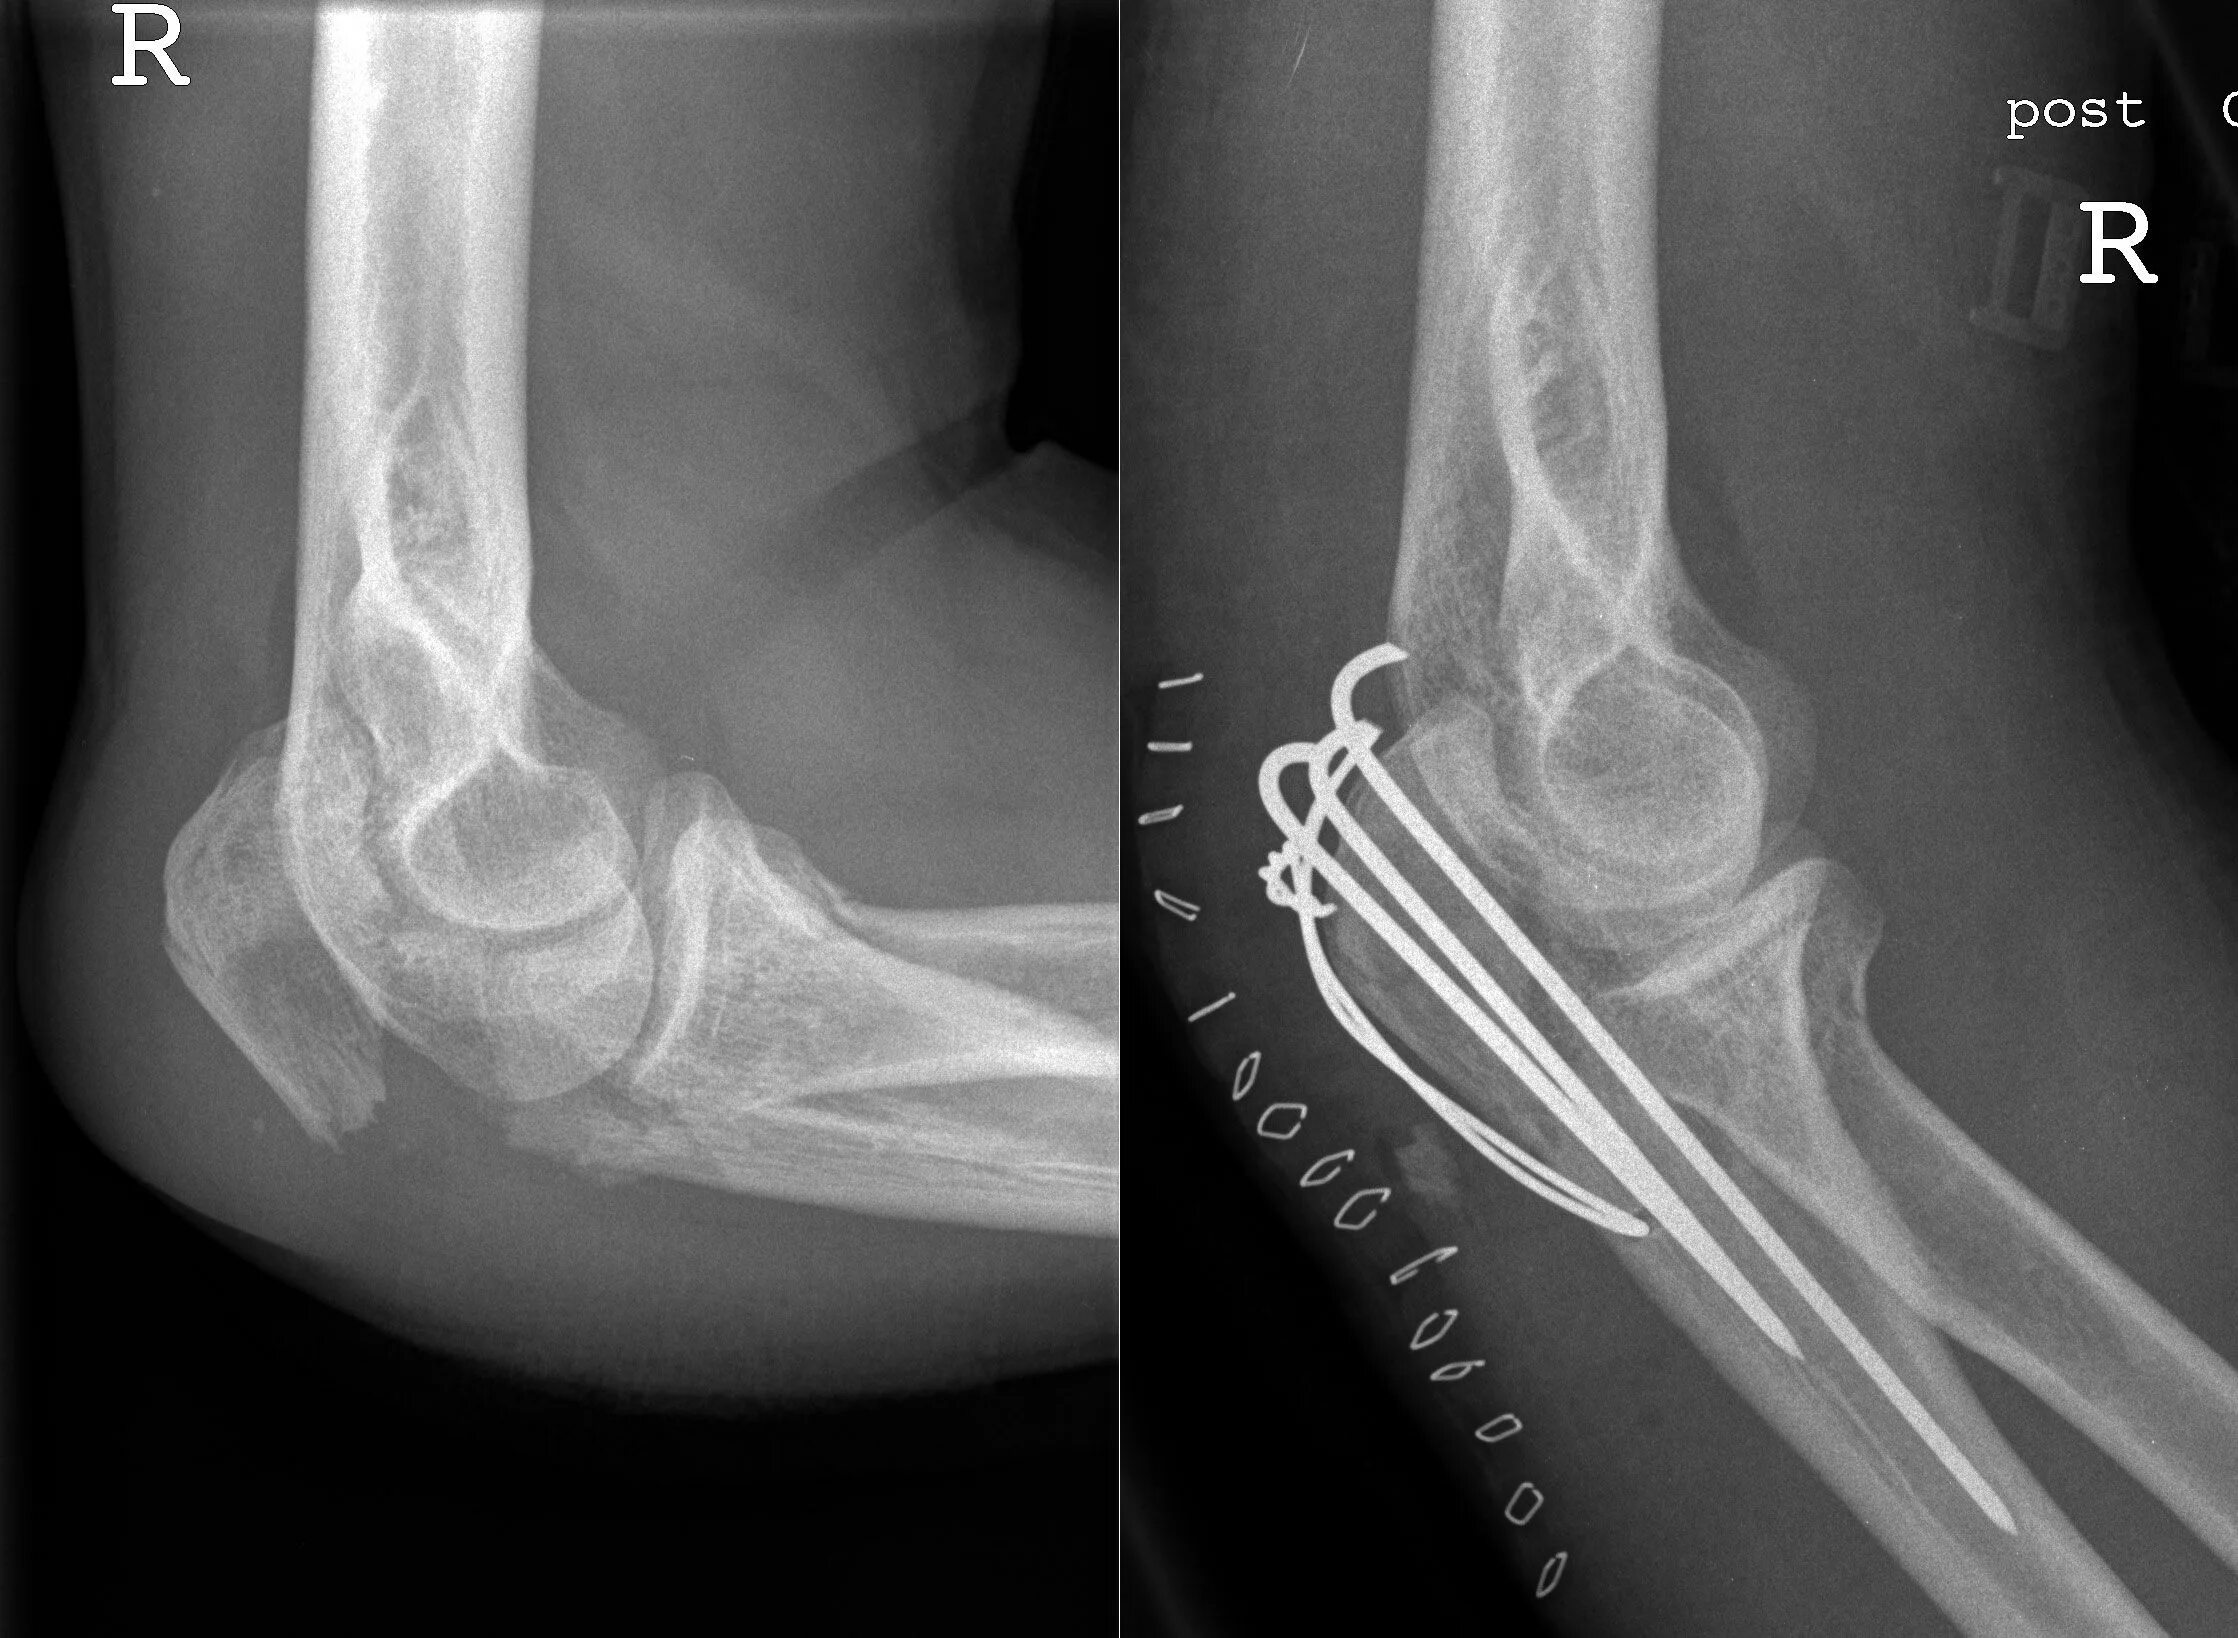

Перелом локтевой